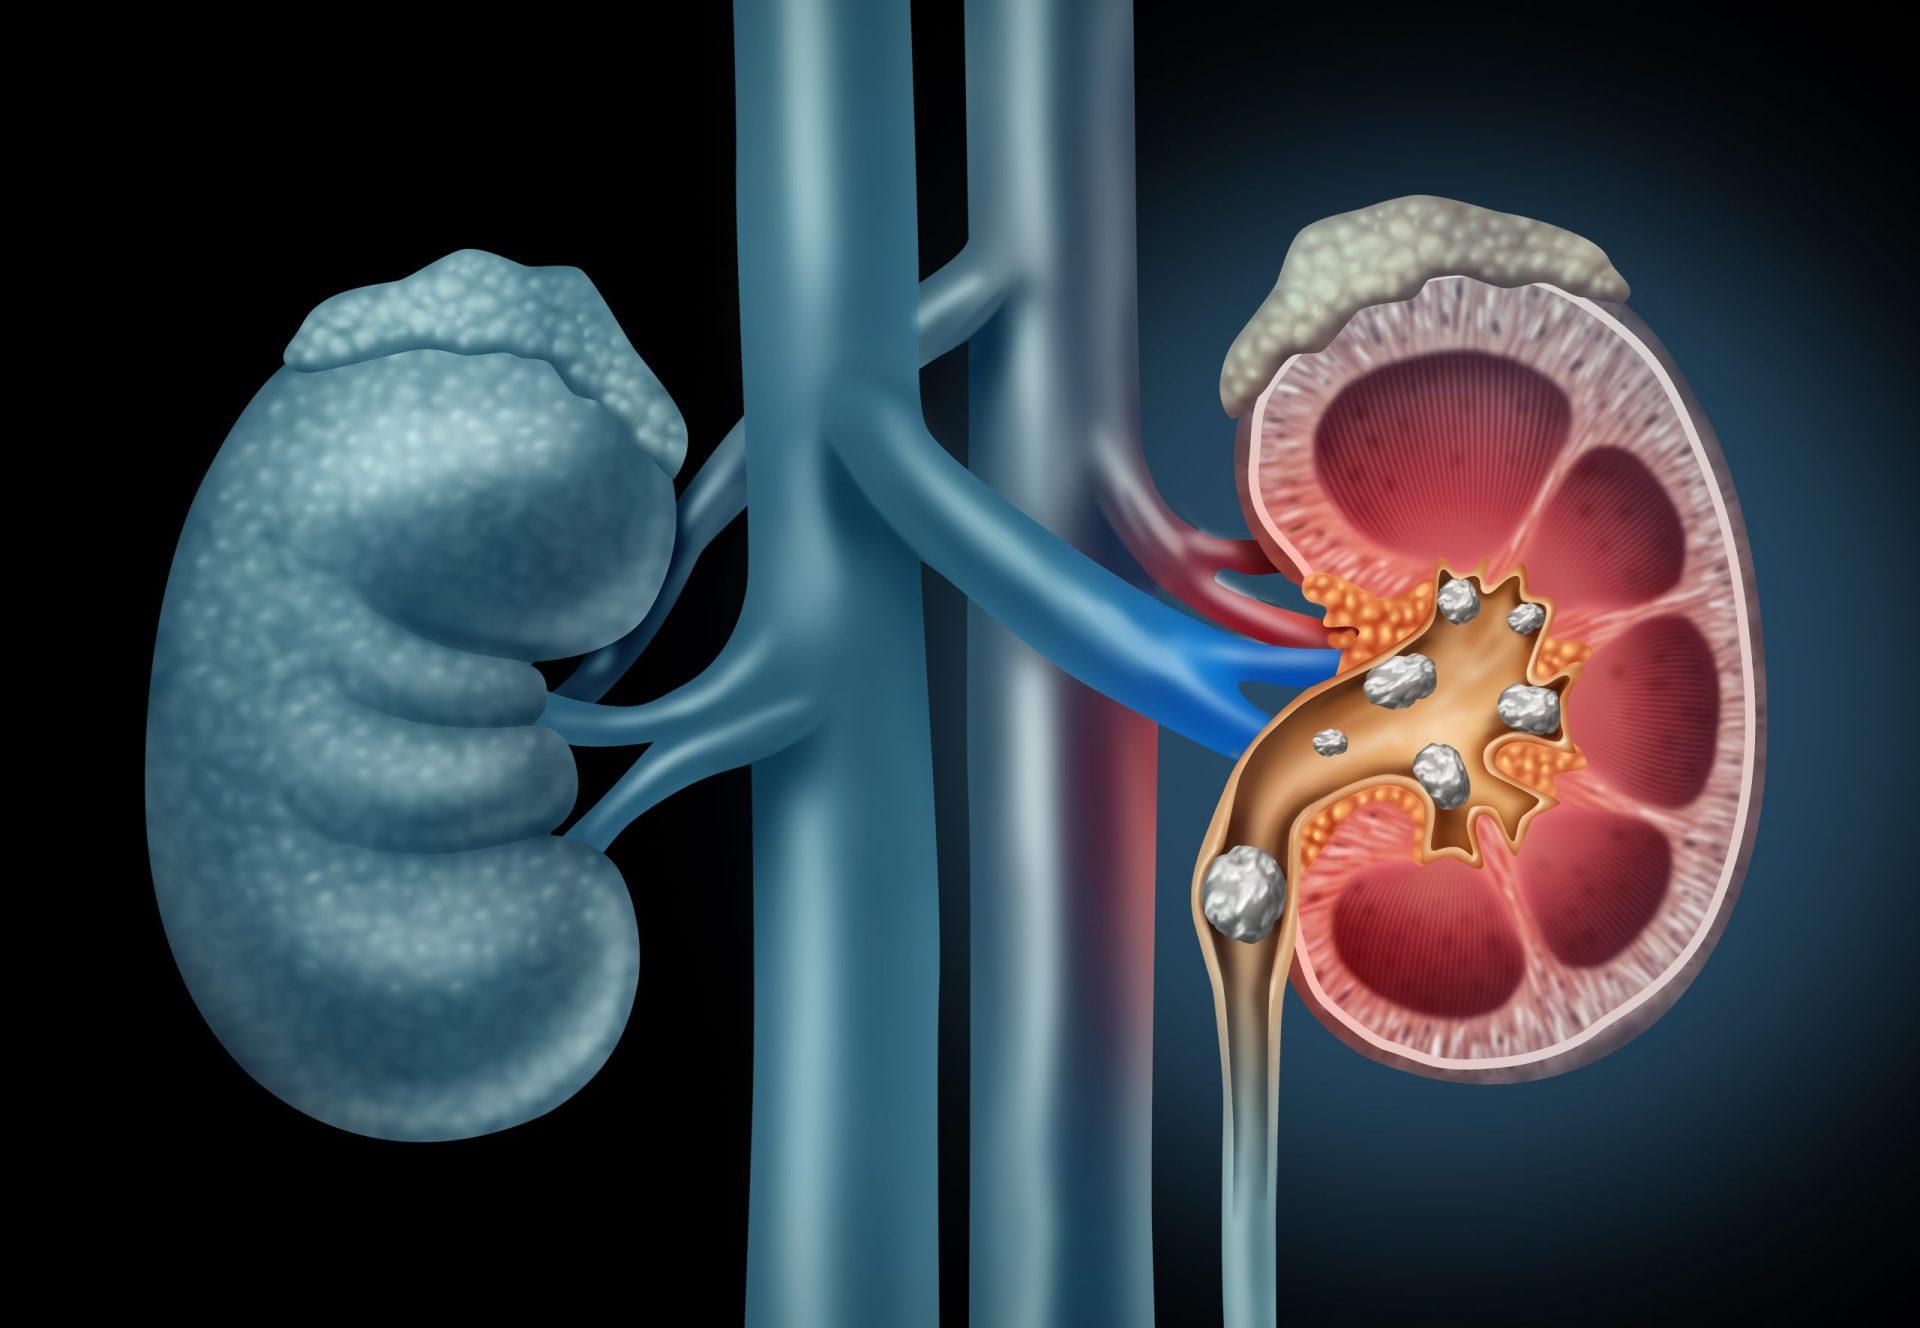

Calculii renali sunt depozite solide formate din minerale și săruri care se pot dezvolta în sistemul urinar. Ele rezultă din cristalizarea unor substanțe prezente în urină și pot varia ca mărime, structură și compoziție, de la granule foarte mici până la mase care pot obstrucționa fluxul urinar. Tipurile frecvente includ calculi pe bază de calciu, acid uric, struvit sau cistin, fiecare având mecanisme de formare și factori predispozanți ușor diferiți.

Formarea calculilor poate fi influențată de factori precum volumul redus de urină, modificări ale compoziției urinare sau anumite condiții metabolice; acești factori pot contribui la creșterea concentrației unor substanțe care favorizează cristalizarea. În multe cazuri, prezența unui calcul poate determina durere sau alte simptome care pot necesita evaluare și management medical adecvat, iar strategiile preventive sau terapeutice sunt adaptate în funcție de tipul și severitatea problemei.

Formarea calculilor apare în general când urina devine supersaturată cu substanțe care cristalizează; condiții care modifică compoziția urinei pot favoriza acest proces. Tipuri frecvente includ calculi pe bază de calciu (de obicei oxalat sau fosfat), acid uric, struvit sau cistină, iar fiecare tip are mecanisme metabolice ușor diferite care pot contribui la formare. Anumite tulburări metabolice, precum și unele medicamente sau intervenții chirurgicale, pot influența echilibrul electroliților sau pH-ul urinei și astfel pot crește predispoziția la pietre.

Factorii care pot crește riscul includ în mod frecvent consumul insuficient de lichide, dietă bogată în sodiu sau în proteine animale, aport crescut de oxalați alimentari și condiții metabolice asociate cu excesul de calciu sau acid uric în urină; obezitatea, istoricul familial și anumite anomalii anatomice ale tractului urinar pot, de asemenea, să joace un rol. Infecțiile urinare recurente pot favoriza apariția calculilor de tip struvit. Pentru resurse suplimentare privind prevenția și cauzele specifice, consultați informații despre calculi renali.